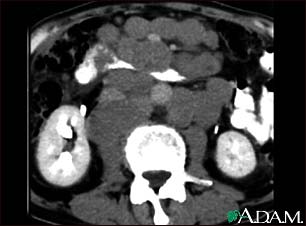

Lymphoma, malignant - CT scan

This abdominal CT scan shows tumor masses (malignant lymphomas) in the area behind the peritoneal cavity (retroperitoneal space).